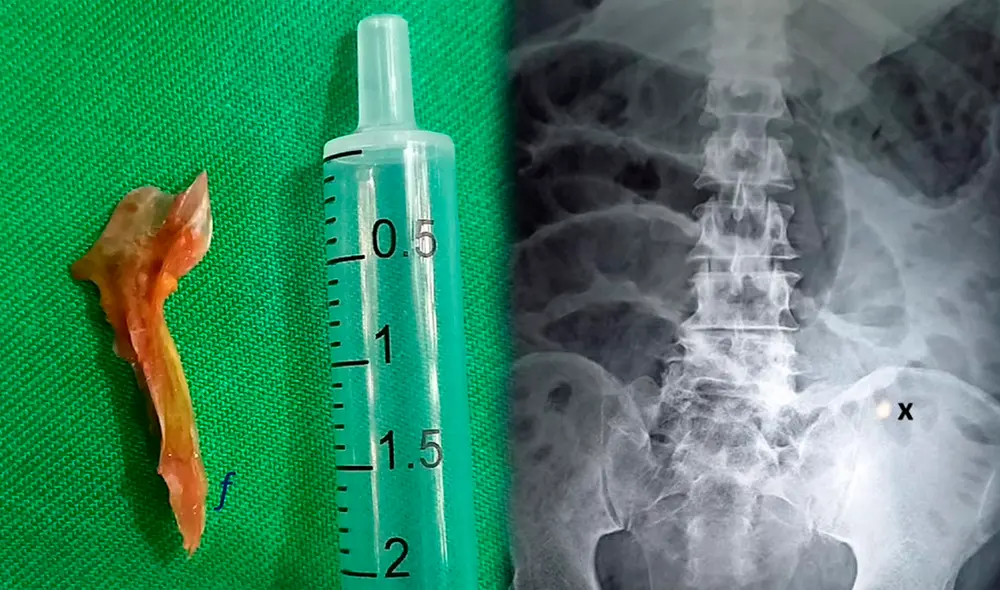

Tras operarlo por dos horas, el personal médico descubrió un pequeño orificio en el intestino del paciente, el cual fue provocado por una espina de pescado de dos centímetros. No obstante, el sujeto no recordaba haber comido dicho fragmento, constató el medio Daily Mail.

Asimismo, los doctores creyeron que el pedazo de hueso había perforado el órgano y había originado que las heces se filtraran e infectaran su pared abdominal, afectando así la salud del sujeto. A pesar de los esfuerzos por parte del personal médico, el hombre falleció de un paro cardíaco ocho horas después de ingresar al centro médico, según el informe.